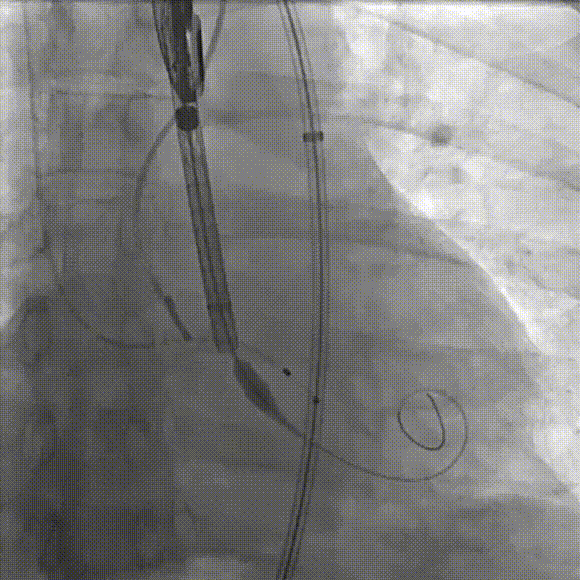

定位

迅速锚定释放至工作位